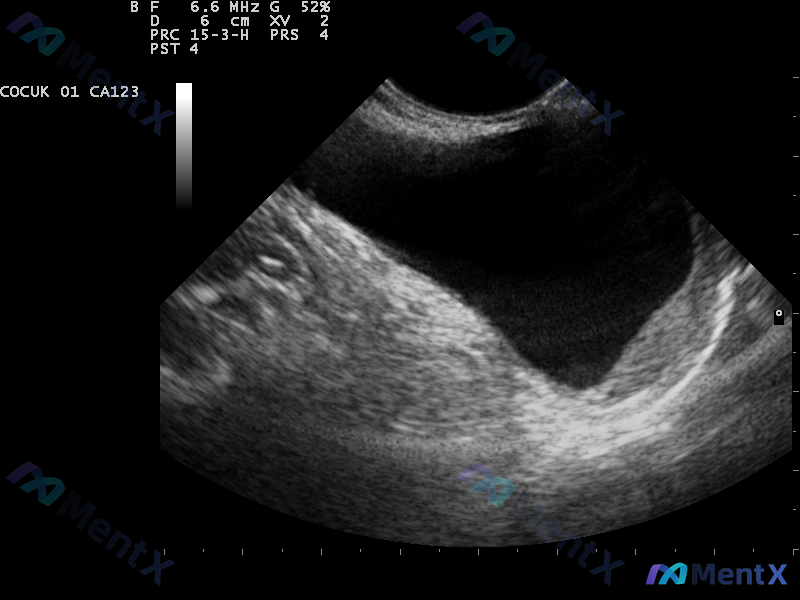

5 岁男童阴囊无痛肿胀,透光阳性,这个解剖对应关系大家熟悉吗?

患者信息:5 岁男童

主诉:睾丸无痛肿胀

现病史:1 岁时首次发现肿胀,逐渐增大。无外伤手术史,无热带地区居住史,免疫接种正常。

- 双侧睾丸肿胀,无压痛

- 波动感明显,透光试验阳性

- 仰卧时肿胀部分减轻

- 咳嗽冲动试验阴性

影像提示:超声显示睾丸周围液性暗区(注:原始影像报告曾有误读,经修正后确认为鞘膜腔积液)。